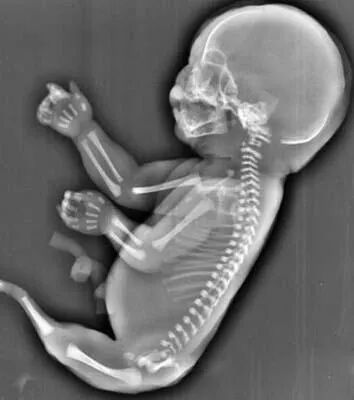

在医学上,有一种罕见的病症叫做美人鱼综合症,胎儿的两条腿紧密结合,看上去就像是美人鱼的尾巴。

27岁的小美(化名)和相爱多年的男友结婚一年后,一个小生命的悄然到来,给整个大家庭送上了一份惊喜,他们俩感觉太幸福了。然而不幸的事情发生了:小美孕25周四维彩超检查发现胎儿下肢无双腿,双下肢合并外形似鱼尾状,据医生了解,这是一种非常罕见的多发性畸形,双下肢合并外形似鱼尾状,俗称“美人鱼综合症”。

无独有偶,一位40岁的二胎妈妈在一次常规的产检中,发现胎儿下肢是两个大腿骨, 并行排列 ,小腿骨好像有点交叉 。医生介绍正常胎儿的下肢是不停地在妈妈肚子里动的, 呈现一个外八字,像这种情况,医生从医40年也是第一次见,后来确诊为美人鱼综合症。因为多数患病的新生儿出生后,只能存活几个小时,就算活下来,也要接受多次手术治疗。最终,在医院的帮助下,这位二胎妈妈选择了终止妊娠。

美人鱼综合症是一种极其罕见的先天性下肢畸形疾病,患者由于血液循环系统在子宫中没有正常发育,从而导致她们的肾脏和其他器官也没有发育完整,他们可能天生就缺失膀胱、子宫、结肠大部分肾脏等多个器官。美人鱼综合症患病几率与连体婴差不多,但夭折率却高得多,因为大部分婴儿天生缺少肾脏之类的重要器官。

(多发畸形)